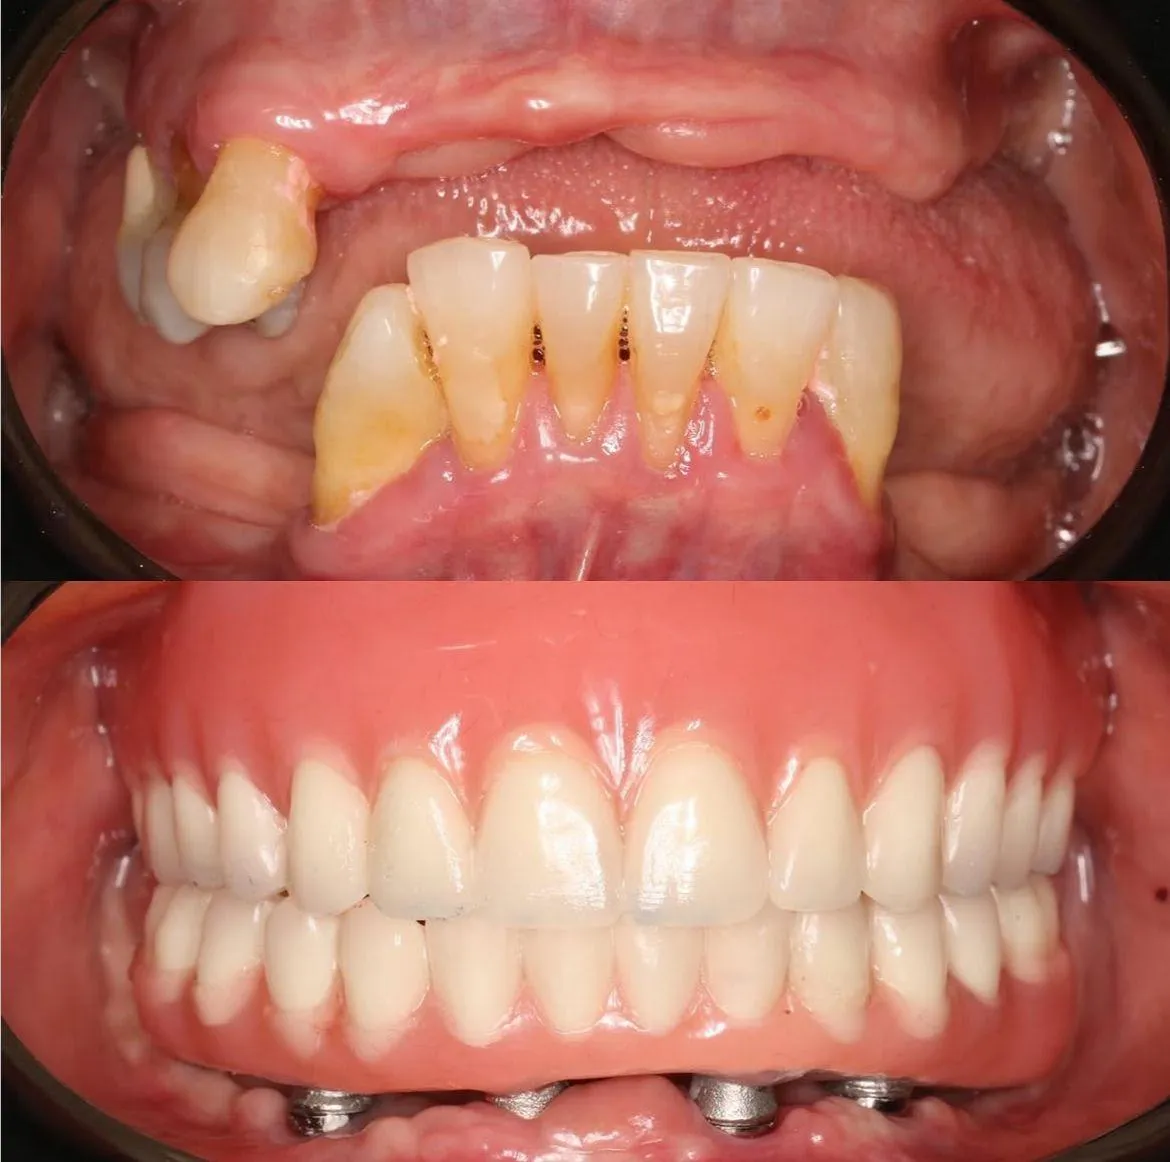

Cada historia es única. Aquí algunas transformaciones que nos llenan de orgullo.